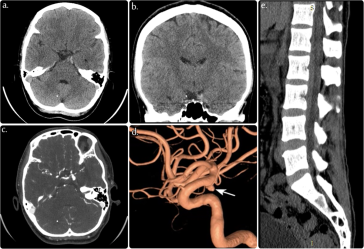

Fatal Ruptured Posterior Communicating Artery Aneurysm A Stark Reminder of Medical Vulnerability